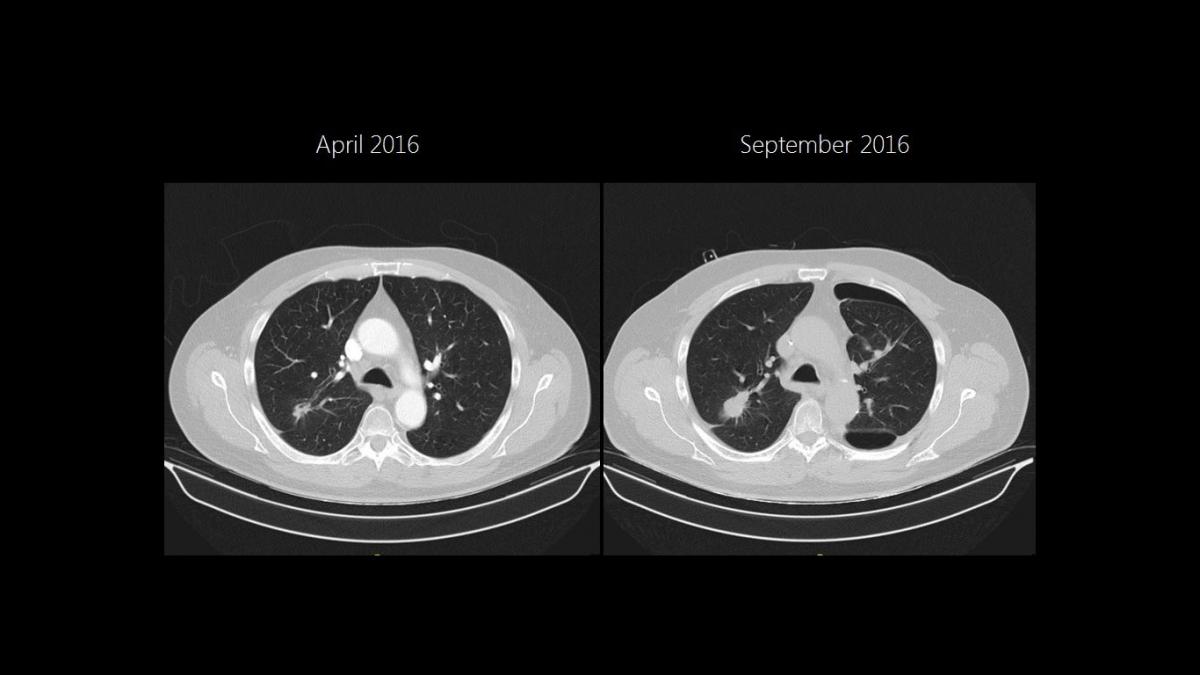

As the RUL was initially accessible for a wedge resection, the LLL nodule was approached first. A non-intubated SI-VATS S6 LLL anatomical segmentectomy was performed in April 2016. Four months later, a segmental S6 bronchopleural fistula was diagnosed and successfully managed with an endobronchial valve. A new chest scan then showed growth of the RUL lesion, requiring a posterior S2 segmentectomy instead of the initial wedge planned (Figure 1).

Figure 1

A posterior segmentectomy was performed through a 4 cm incision placed in the 5th right intercostal space, involving intercostal blocks with bupivacaine of the 3rd to 7th intercostal spaces, as shown in the video.